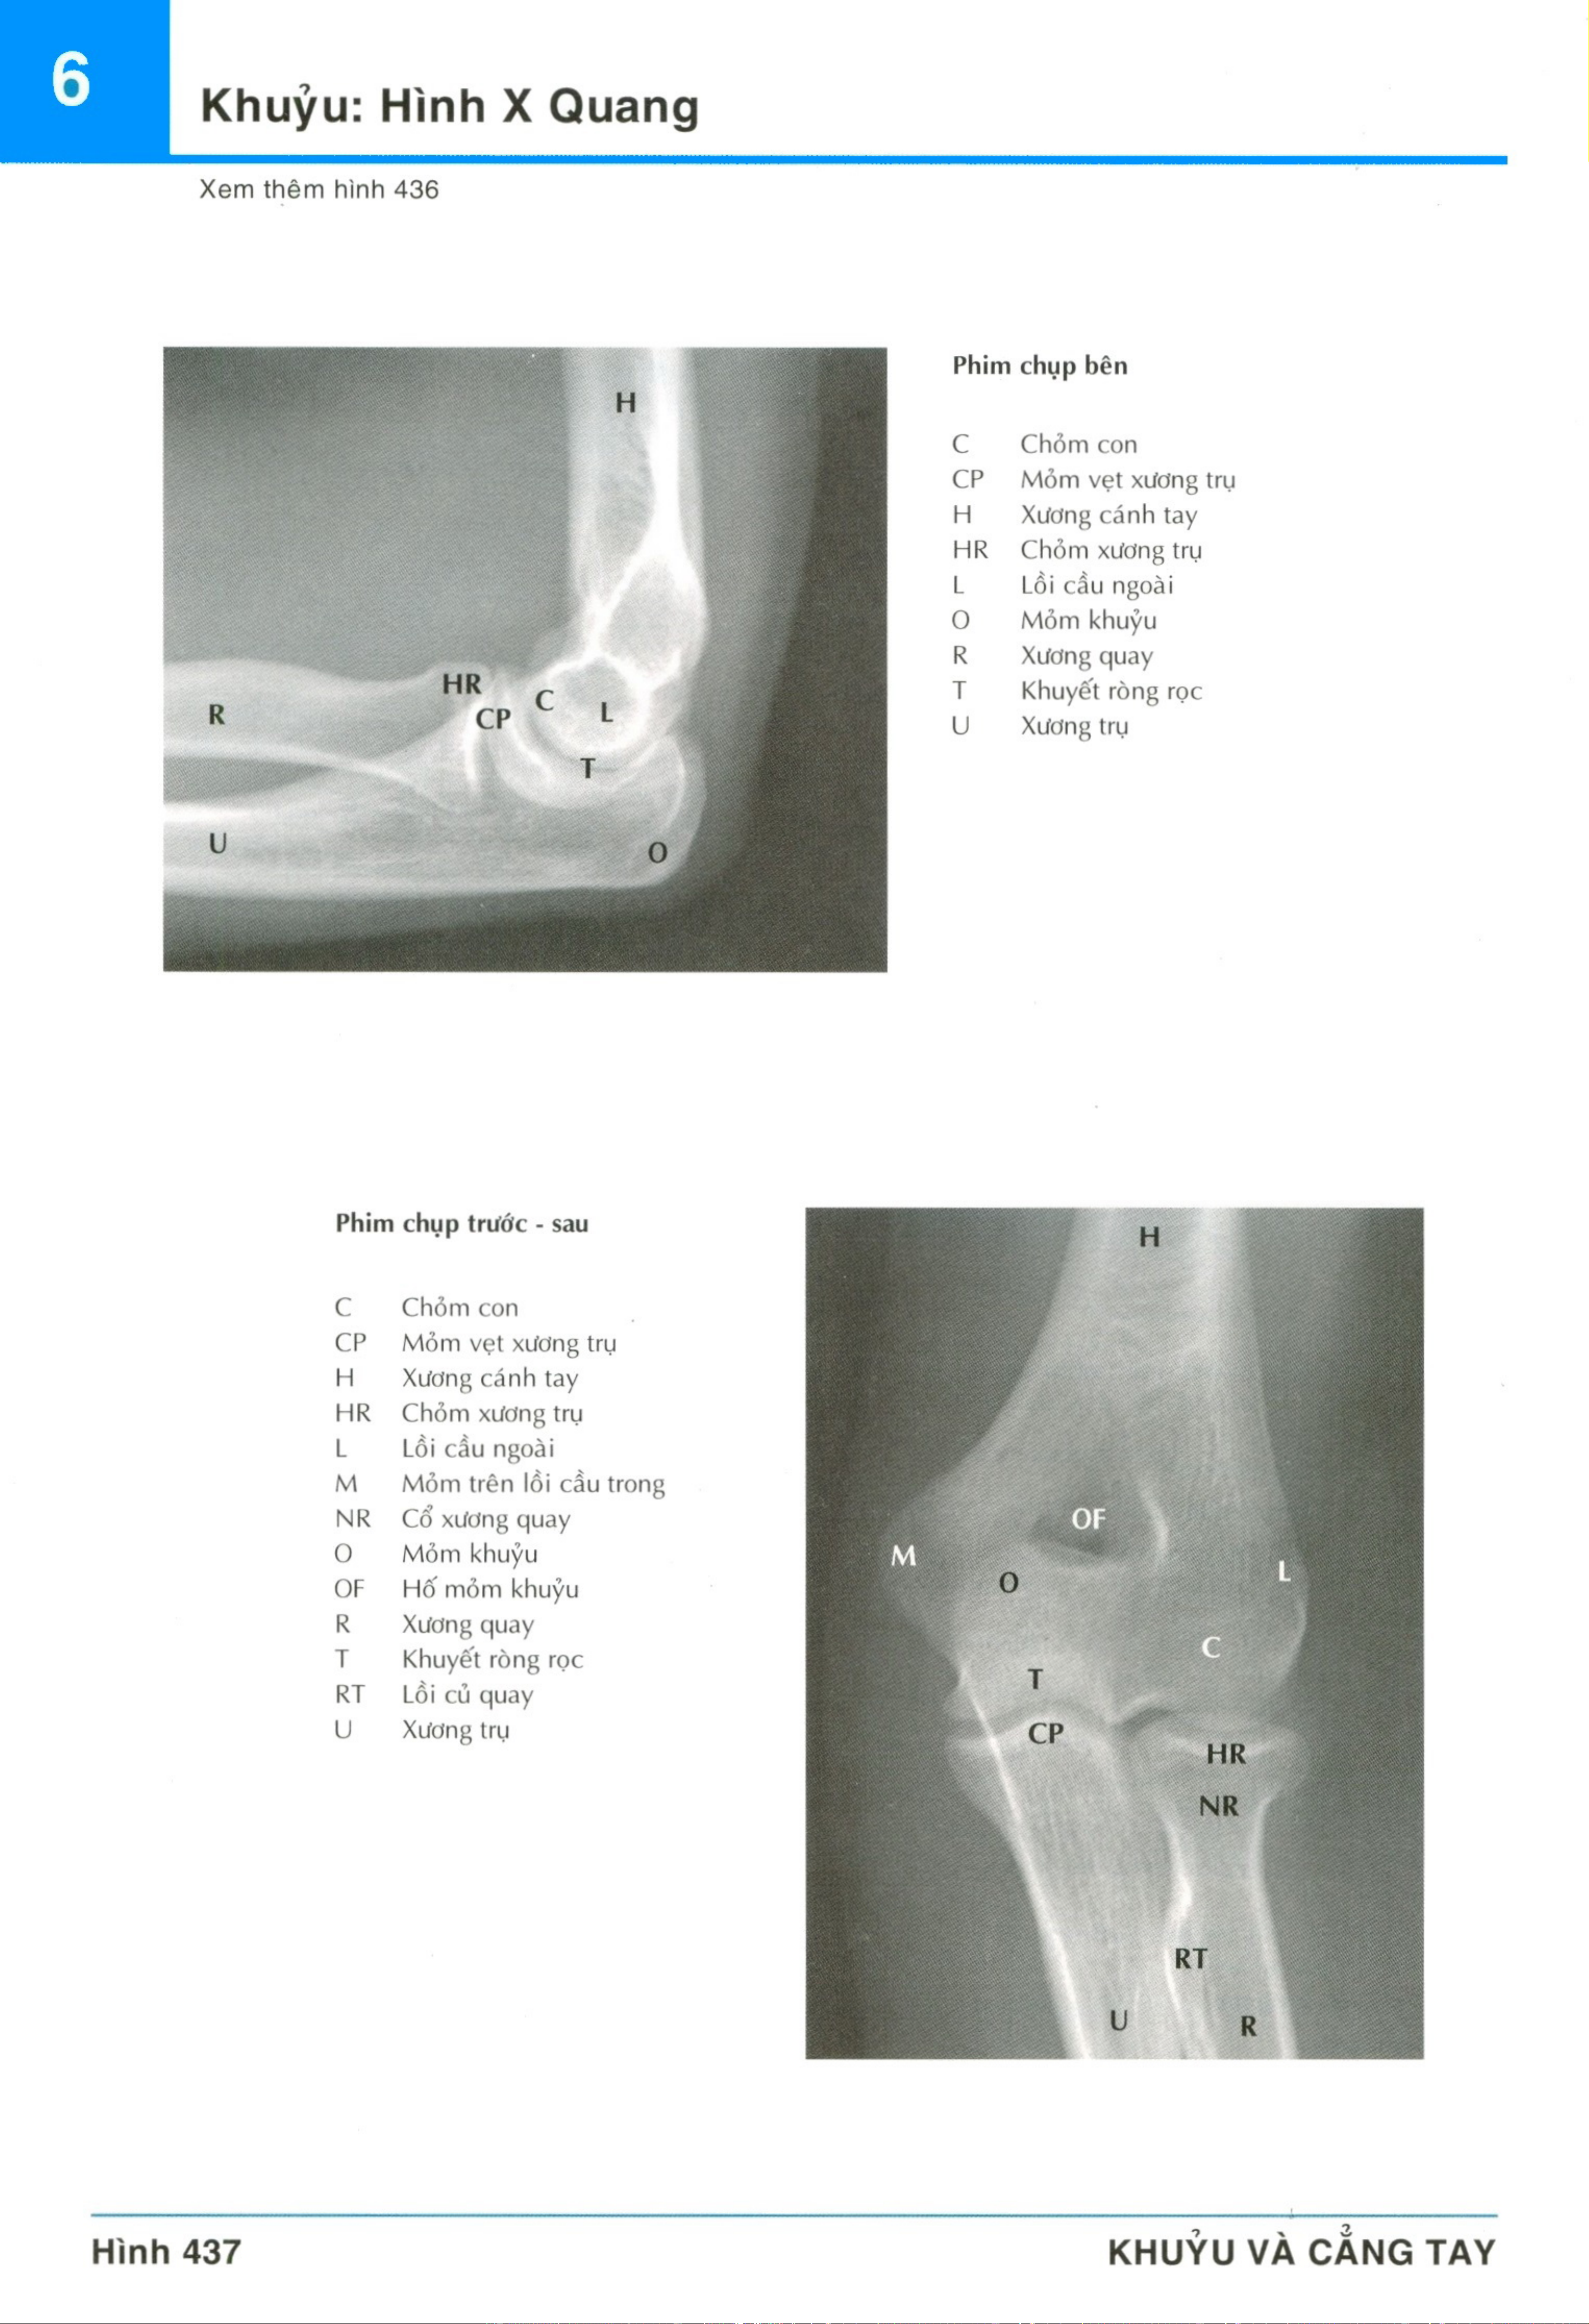

Chương 6: Chi trên môn Giải phẫu | Trường Đại học Y Dược, Đại học Quốc gia Hà Nội

Chương 6: Chi trên môn Giải phẫu | Trường Đại học Y Dược, Đại học Quốc gia Hà Nội. Tài liệu được sưu tầm giúp bạn tham khảo, ôn tập và đạt kết quả cao. Mời bạn đọc đón xem.